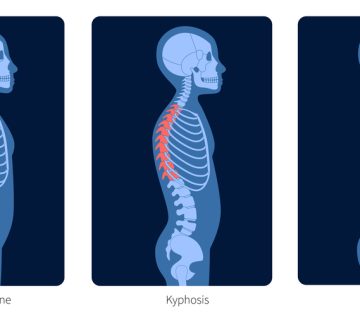

اسکولیوز نوروماسکولار (Neuromuscular Scoliosis یا به اختصار NMS) نوعی انحراف ستون فقرات است که در کودکانی دیده میشود که دچار بیماریهای عصبی یا عضلانی هستند. برخلاف اسکولیوز ایدیوپاتیک نوجوانان که علت مشخصی ندارد و در دوران رشد به وجود میآید، اسکولیوز نوروماسکولار ثانویه به یک بیماری زمینهای و شرایط عصبی یا عضلانی است.

در این کودکان، ضعف یا اسپاسم (سفتی) عضلات، عدم تعادل و فقدان کنترل حرکتی باعث میشود ستون فقرات نتواند صاف بماند. به مرور، ستون فقرات دچار یک انحنای بزرگ و گسترده و معمولاً C شکل میشود که هم ناحیهی میانی پشت (سینهای) و هم کمر را درگیر میکند.

- ایجاد انحنای بلند و C شکل (برخلاف انحنای S شکل در اسکولیوز ایدیوپاتیک).

- عوارض ثانویه مانند تغییر شکل قفسه سینه و کاهش حجم ریهها.